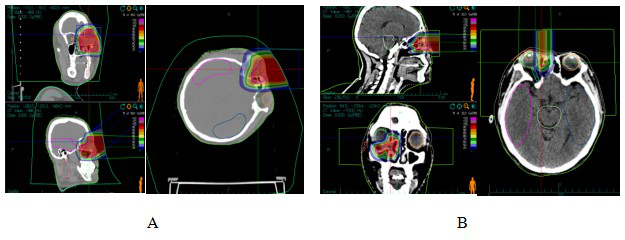

Case 1: Female, 44 years old, squamous carcinoma of the right lacrimal sac. She visited our hospital in July 2022, and on examination, she was found to have a swelling of about 3 cm × 4 cm in size in the lower eyelid of her right eye, with mild limitation of eye movement in all directions. After a thorough examination and evaluation of the patient, the patient was treated on 20 July 2022 with CIRT. The prescribed dose for the first course: PTV 40Gy (RBE)/10fx; lateral position, 2D homogeneous scanning, and the dose distribution is shown in Figure 1A.The prescribed dose for the second course: PTVboost 24Gy (RBE)/6fx; supine position, 2D homogeneous scanning. The total dose to the tumour area was 64 Gy (RBE)/16 F, 4.0 Gy (RBE)/F, and 5 F/w, and the dose distribution is shown in Fig. 1B.Comparison of the dose distribution of axial images between CIRT and volume-modulated intensity-adjusted radiotherapy (VMAT) plans while both fulfilling the prescriptive requirements, and the range of the surrounding normal tissues irradiated at low doses was significantly smaller for the CIRT plan compared to the VMAT plan, see Fig. 2A and The efficacy of CIRT was compared by imaging data before and after treatment, and the patient's efficacy was assessed according to the Response to Evaluation Criteria for the Evaluation of Solid Tumours (RECIST) 1.1, and the efficacy of treatment reached a complete remission (CR) 3 months after treatment, as shown in Fig. 3. During the CIRT treatment period and in the first month after the treatment, the patient developed grade 1 acute radiation conjunctival injury; 3 months after the end of radiotherapy, she developed dry eyes, and the use of eye drops for a long time was considered to be grade 1 radiation conjunctival damage, which was considered to be grade 1 radiation conjunctival damage. , considered grade 1 radiation conjunctival injury (RTOG Acute Radiation Injury Grades), no late adverse events greater than grade 2 were observed.Combination of a target (cetuximab) during CIRT treatment, with disseminated rash on the face during the treatment period, grade 1 on the Common Terminology Evaluation Criteria for Adverse Events. As of September 2024, the patient is currently disease-free and continues to be followed for the long term.

Figure 1 CIRT dose distribution in patients with dacryocystosquamous cell carcinoma

Note: Figure 1A: One course CIRT dose distribution. Figure 1B: Two course CIRT dose distribution

Figure 2 VMAT plan and carbon ion plan dose distribution in patients with dacryocystosquamous cell carcinoma

Note: Figure 2A: VMAT plan dose distribution in patients with dacryocystosquamous cell carcinoma. Figure 2B: Carbon ion plan dose distribution in patients with dacryocystosquamous cell carcinoma.